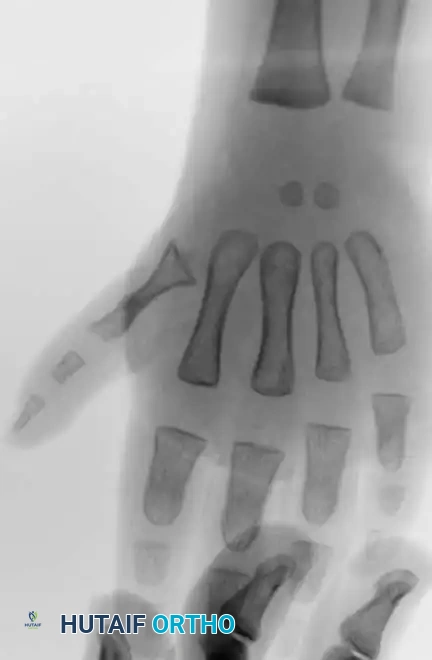

Image

Radiographic evaluation is mandatory to assess the presence and stability of the first metacarpal and the carpometacarpal joint, which dictates the choice between reconstruction and pollicization.